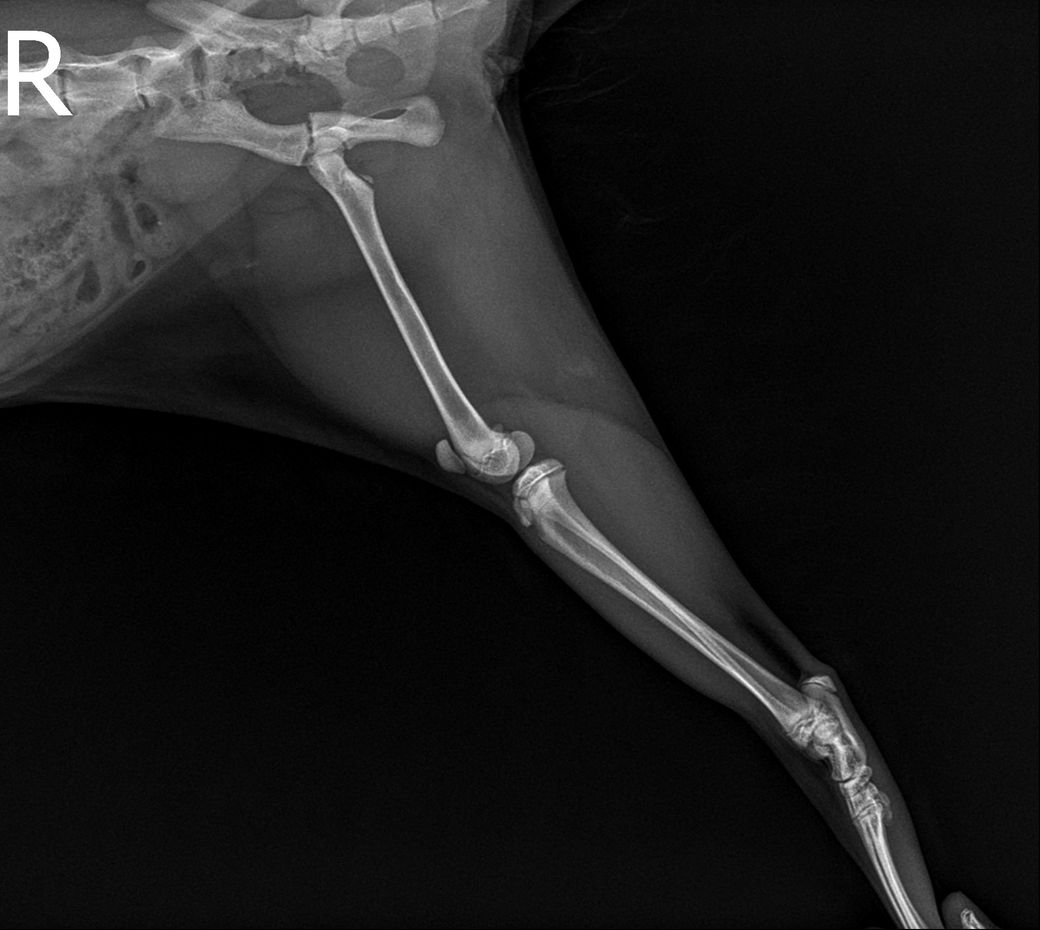

고양이 고관절 골절 진단받았는데 병원에서는 수복수술 해야한다고 하는데 자연적으로 붙는곳이아닌가요 ? 그리고 예후가 괜찮을까요 ? 수술한다고해서? 예후가 안괜찮다하면 어떤식으로 안좋을까요 ?

예, 사진상 우측 고관절의 관절면이 포함된 골절이기에 하중이 가해지는 장소인 바 자연 치유는 후천적 기형을 유도하게 되고, 수술을 하더라도 관절면이 포함된 상태로 예후는 불량한 수준입니다. 때문에 단순한 유합수술이 아닌 대퇴골두골목절단술을 동반해야 합니다.